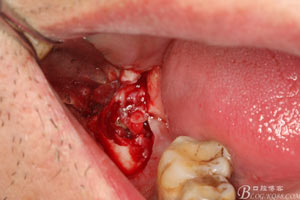

圖7.高速牙鉆去骨。逐漸可見(jiàn)48的牙冠